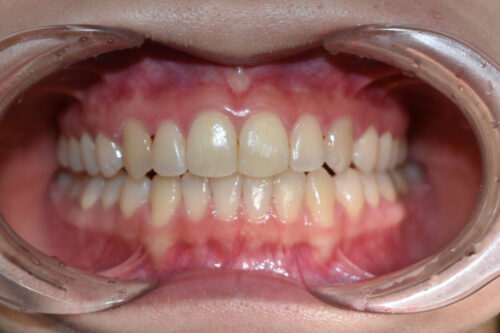

ワイヤー矯正治療9か月後です。

本症例も

矯正治療の精密検査後

非抜歯矯正治療計画を立案しました。

全額矯正治療 88万円、3~4週に一回来院

歯科矯正用アンカースクリュー(デュアル・トップオートスクリュー)上顎左右2本(25000円x1本分 提携医院にて)

ワイヤー期間 9か月, 14回来院

マウスピース型カスタムメイド矯正歯科治療を用いた矯正歯科治療装置を利用した矯正治療 5か月間 33000円、

開咬は 決して 難しいケースでは ございません。